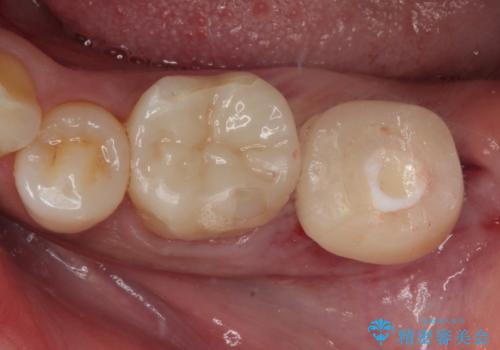

抜歯即時インプラントで治療期間を大幅短縮!抜歯からセラミックまでを3か月で完了

- 3ヶ月

- 2-5回

- 44万円(税込)費用は治療当時の料金となります